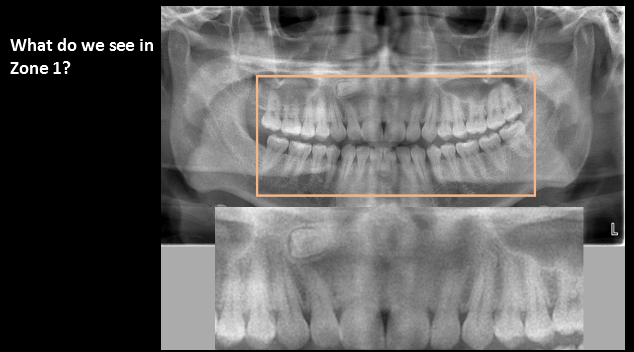

What do we see in Zone 1?

supernumerary teeth/impacted tooth